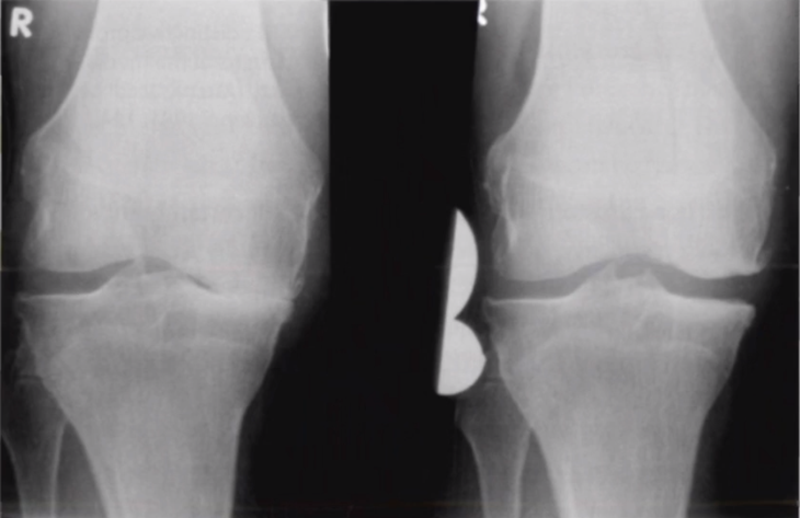

二、单髁置换的适应证——外翻应力片

屈曲20°外翻应力:看外侧软骨

外翻应力片可以辅助评价外侧间室关节软骨厚度是否正常,以及内侧副韧带功能是否完整。外侧全层软骨、外侧有骨赘的情况下都不是禁忌证,如外侧出现软骨磨损则为禁忌证。

外翻应力片还可以观察内侧间隙,如内侧副韧带出现挛缩,间隙狭窄,那么此时不适合单髁。

检查时注意X线的投照角度要平行于关节线方向,以保证准确。

可以矫正畸形,恢复关节间隙和MCL张力